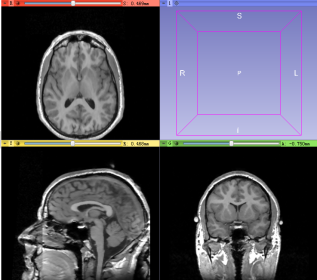

- 1 Load MRI/CT images of brain